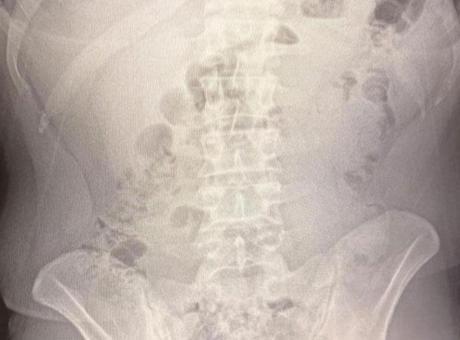

Adreste yapılan arama sırasında ekipler, şüphelilerden birinin üstünde 1 adet kapsül ele geçirdi. Şüphe üzerine tüm şüpheliler hastaneye götürüldü ve yapılan röntgen kontrollerinde 3 kişinin midelerinde kapsül içine gizlenmiş metamfetamin tespit edildi.

Hastanede tedavi altına alınan şüphelilerin vücudundan kapsüller çıkarılırken, adreste ele geçirilenlerle birlikte toplam 1 kilo 516 gram metamfetamin ele geçirildi.